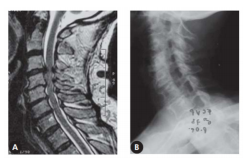

Uma paciente de 75 anos começou a apresentar perda da destreza manual e dificuldade para escrever e fechar os botões das roupas, evoluindo, ao longo de anos, com fraqueza e dormência de membros superiores, predominantemente distal, dor cervical persistente, às vezes intensa, seguida de atrofia de mãos e paraparesia. Foi, então, levada pelos filhos ao médico neurologista e realizou Ressonância Magnética (RM) de crânio, que estava normal, mais Radiografia e RM de coluna cervical, mostradas a seguir. Qual é a principal hipótese diagnóstica para o caso?